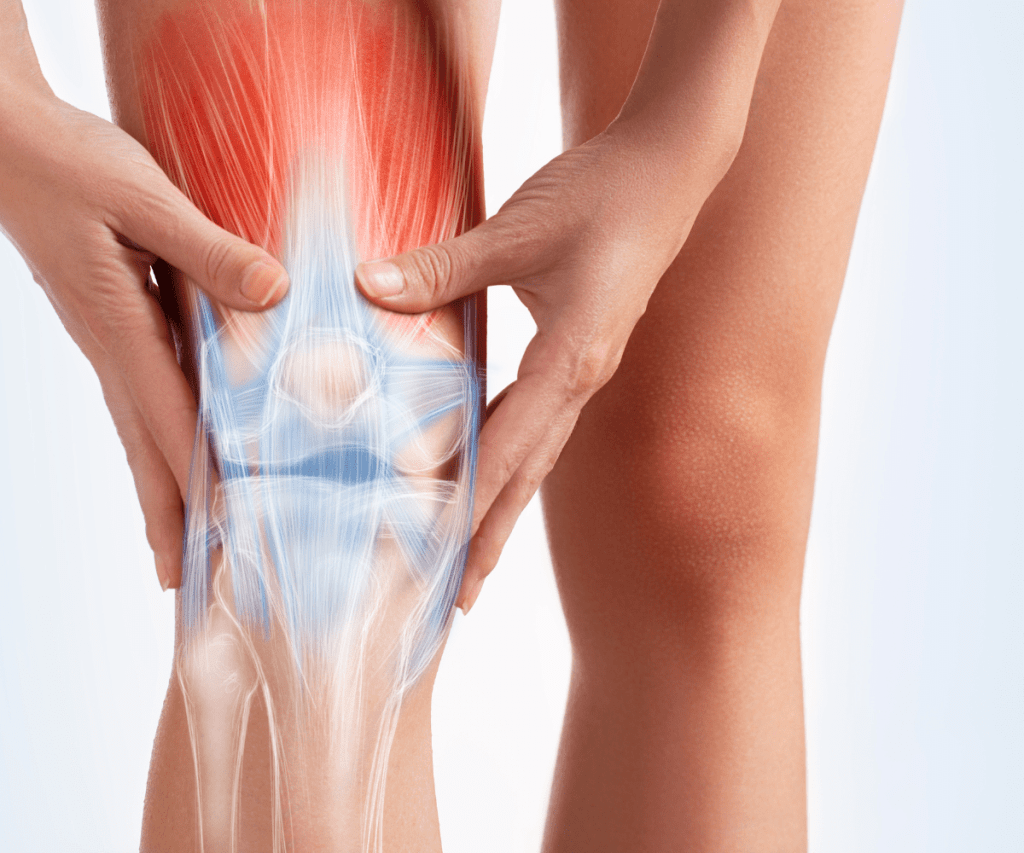

Najpogostejši pojav v kolenu je obraba sklepnega hrustanca ali artroza.

Običajno se pojavi zaradi:

- predhodne okvare kolena (vnetje, okvara meniskusa, sprememba pogačice),

- povečane telesne teže

- spremembe na stopalih.

Sklepni hrustanec postane razpokan in nazobčan.

Med gibanjem se poškodovan sklepni hrustanec brusi in tanjša. Delci poškodovanega in odmrlega hrustanca dražijo sklepno ovojnico, ki je močno oživčena in povzročijo njeno vnetje.

Simptomi:

- bolečina,

- oteklina,

- zmanjšana gibljivost kolena

- lahko se sliši škrtanje,

- upadla štiri-glava stegenska mišica,

- sklepna špranja je na RTG sliki močno zožena, kost pod hrustancem pa sklerotična (okorela).